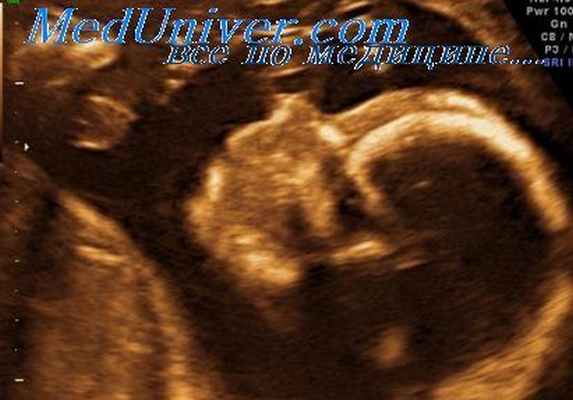

Наряду с пороками развития описаны хромосомные аберрации [10]. Особое внимание уделяется проведению пренатальной диагностики. Пренатально пентада Кантрелла может быть выявлена при ультразвуковом исследовании уже с 10-й недели беременности. Ультразвуковая диагностика в 2D-реконструкции в первом триместре и дополнительное использование 3D-режима улучшает визуализацию аномалий плода практически в любом его положении [11]. Если по данным ультразвуковой диагностики выставлен диагноз пентада Кантрелла, целесообразно проведение хромосомного анализа, в связи с указаниями на возможную ассоциацию с трисомией, а также с синдромом Тернера [9]. Кроме ультразвуковой диагностики проводится магнитно-резонансная визуализация, которая в сочетании с эхокардиографией плода позволяет провести оптимальную оценку комбинации пороков при данной врожденной патологии. Прогноз определяется тяжестью поражения сердца и других сочетанных с ним аномалий.

Наряду с пороками развития описаны хромосомные аберрации [10]. Особое внимание уделяется проведению пренатальной диагностики. Пренатально пентада Кантрелла может быть выявлена при ультразвуковом исследовании уже с 10-й недели беременности. Ультразвуковая диагностика в 2D-реконструкции в первом триместре и дополнительное использование 3D-режима улучшает визуализацию аномалий плода практически в любом его положении [11]. Если по данным ультразвуковой диагностики выставлен диагноз пентада Кантрелла, целесообразно проведение хромосомного анализа, в связи с указаниями на возможную ассоциацию с трисомией, а также с синдромом Тернера [9]. Кроме ультразвуковой диагностики проводится магнитно-резонансная визуализация, которая в сочетании с эхокардиографией плода позволяет провести оптимальную оц.